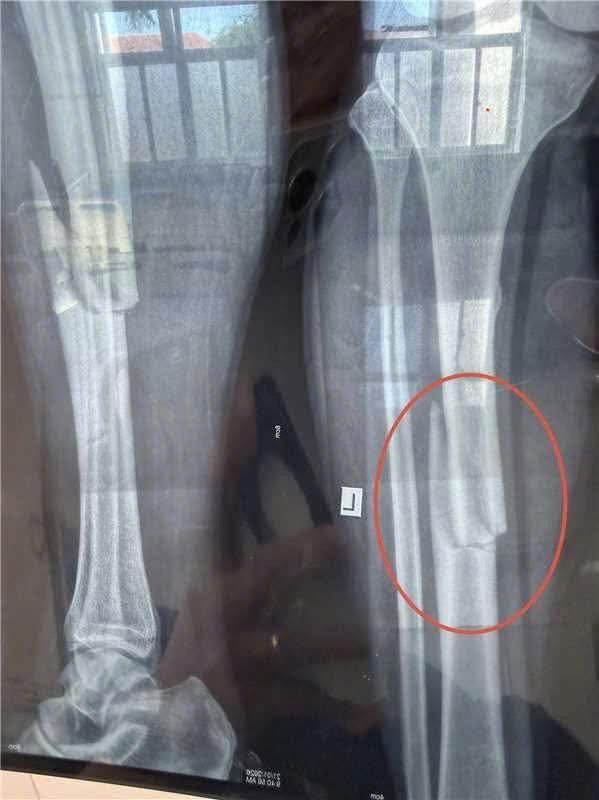

TNLĐ trong lúc làm việc ở PĐ, làm nam thanh niên chan’ thư:ơng

Tết tới rồi làm việc chú ý nha mọi người

khu công nghiệp Phước đông Tây ninh